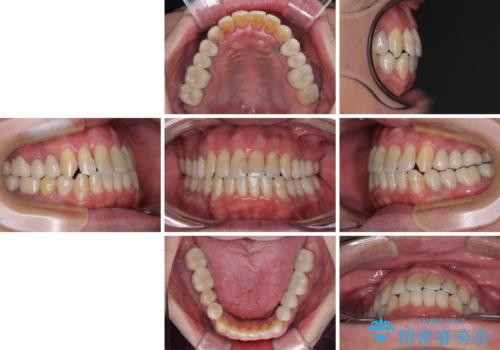

- 飛び出している上顎前歯と、奥歯に多くある銀歯を気にして来院された患者様です。

マウスピースで矯正を行いたい反面、一旦早めに前歯を整えたいというご希望があったため、まずは上顎前歯をワイヤー装置で整え、その後インビザラインにて仕上げていくこととしました。

矯正治療後には、奥歯の銀歯をすべてセラミックにて補綴治療することとしました。

ワイヤー矯正を併用したことで、上顎前歯はあっという間に整いました。

補綴治療中に前歯のデコボコが戻ってしまったため、補綴治療後にインビザラインを1セット追加して仕上げました。